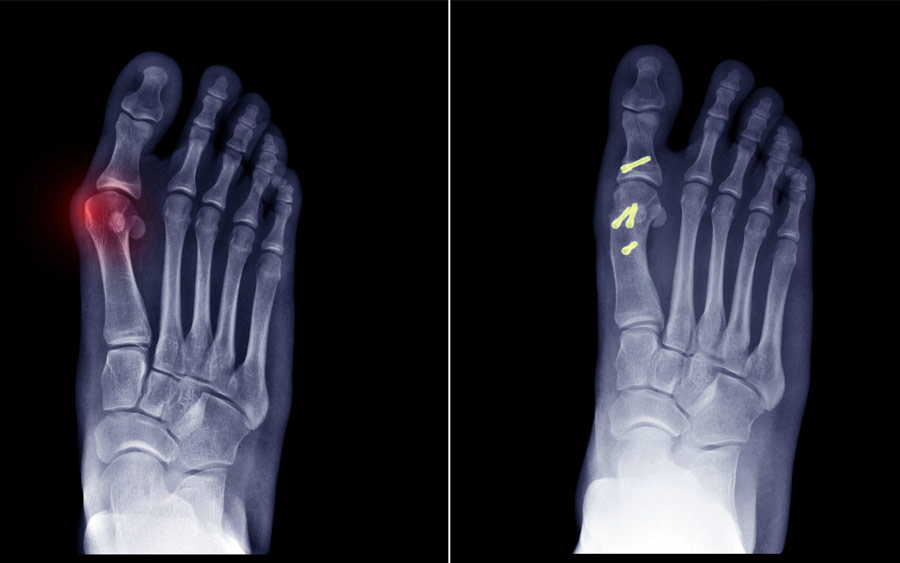

Οι ακτινογραφίες υπό φόρτιση είναι χρήσιμες για τη μέτρηση ειδικών παραμέτρων κατά τον προεγχειρητικό σχεδιασμό, όπως η γωνία βλαισού μεγάλου δακτύλου (φυσιολογικά <15°), η διαμετατάρσια γωνία (<9°), η γωνία μεταξύ της αρθρικής επιφάνειας της κεφαλής του 1ου μεταταρσίου με τον άξονα του 1ου μεταταρσίου (<10°) και η γωνία μεταξύ των αξόνων της εγγύος και της τελικής φάλαγγας του μεγάλου δακτύλου (<10°). Ελέγχεται επίσης η προς τα έξω παρεκτόπιση των σησαμοειδών οστών, η επαλληλία και τυχόν εκφυλιστικές αλλοιώσεις της 1ης μεταταρσιοφαλαγγικής άρθρωσης.

Οι επεμβάσεις μαλακών μορίων (τροποποιημένη τεχνική McBride) γίνονται σε νεαρές γυναίκες με πολύ ήπια νόσο, σχεδόν πάντα συνοδεύονται από οστεοτομία. Οι επεμβάσεις περιφερικής οστεοτομίας 1ου μεταταρσίου (συχνότερα η Chevron) και εγγύος φάλαγγος μεγάλου δακτύλου (οστεοτομία Akin) ενδείκνυνται σε ήπια νόσο (διαμετατάρσια γωνία <13°).

Οι επεμβάσεις κεντρικής οστεοτομίας (συχνότερα η Scarf) ή ο συνδυασμός περιφερικής και κεντρικής οστεοτομίας 1ου μεταταρσίου ενδείκνυνται σε μεγαλύτερες παραμορφώσεις (διαμετατάρσια γωνία > 13°).